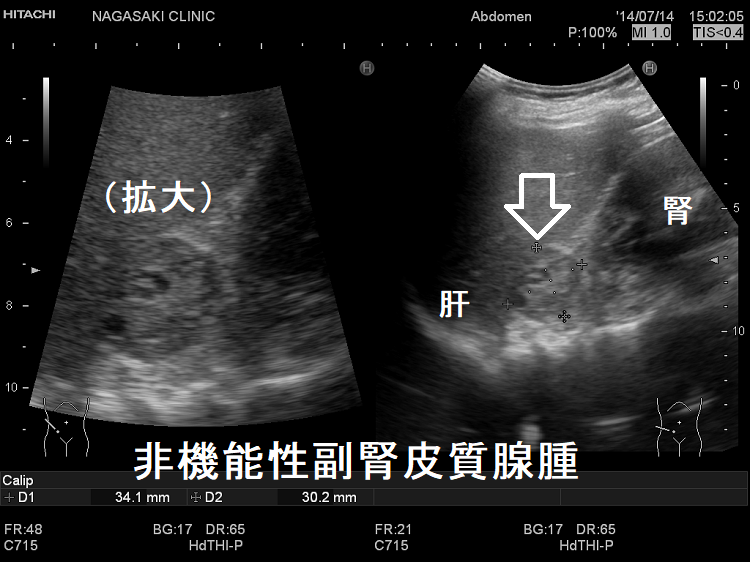

(右)非機能性副腎皮質腺腫:内部は不均一・粗で、当初、副腎癌か褐色細胞腫が疑われました。摘出標本で非機能性副腎皮質腺腫が確定。